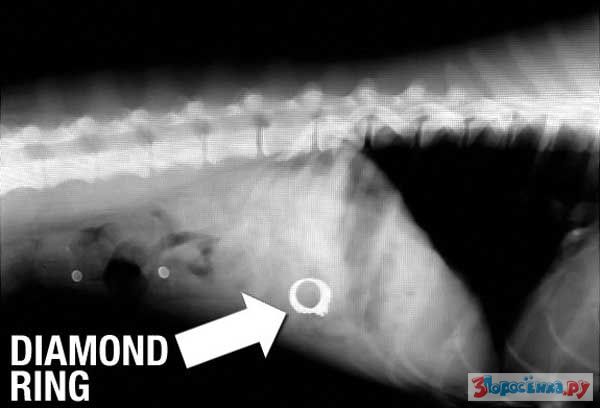

Нет ничего не перевариваемого

Некоторые собаки видимо полагают что их желудок способен переварить все на свете.